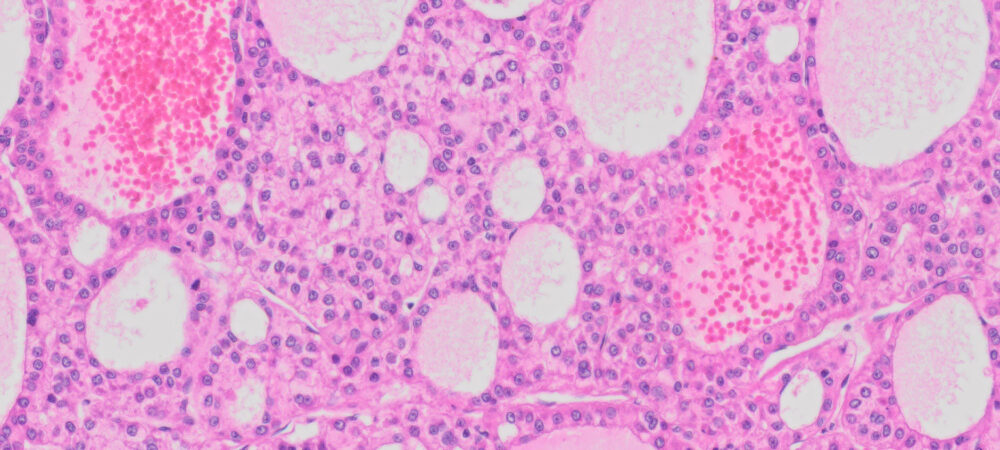

| HuPS-08003TA | Human Liver | Hepatocellular carcinoma and adjacent normal tissue | Female | 65 | 5 µm | Ki67 |

Human tissue was fixed in formalin immediately after excision and embedded in paraffin. The tissue sections were 5 µm in thickness and mounted each on positively charged glass slides.